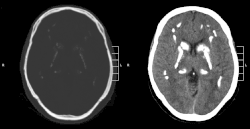

![]() Obraz choroby Fahra w tomografii komputerowej | |

Choroba Fahra, zespół Fahra, idiopatyczne zwapnienie jąder podstawy, idiopatyczne zwapnienie zwojów podstawy – rzadka, uwarunkowana genetycznie choroba obejmująca ośrodkowy układ nerwowy, dziedziczona w sposób autosomalnie dominujący[1]. W sposób dominujący dziedziczone są mutacje genów SLC20A2[2]. Charakteryzuje się występowaniem obustronnych i symetrycznych zwapnień w jądrach podstawnych, które mogą pojawiać się także w innych strukturach anatomicznych mózgowia (np. korze mózgowej, móżdżku)[3][4].